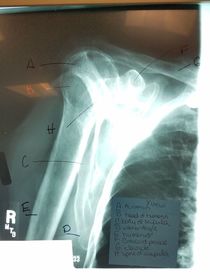

A. greater tubercle (tuberosity) B. intertubercular groove (bicipital) C. surgical neck D. head E. anatomic neck F. lesser tubercle (tuberosity) G. deltoid tuberosity H. humeral body (shaft)

A. humeral head B. greater tubercle C. intertubercular groove (bicipital) D. lesser tubercle E. anatomic neck F. surgical neck G. humeral body